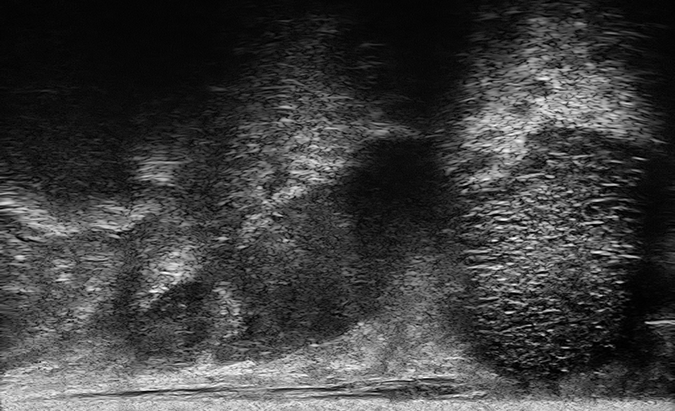

PRI-MUS 5

Irregular Shadowing or Mixed-echo lesions or Irregular Prostate/PZ border